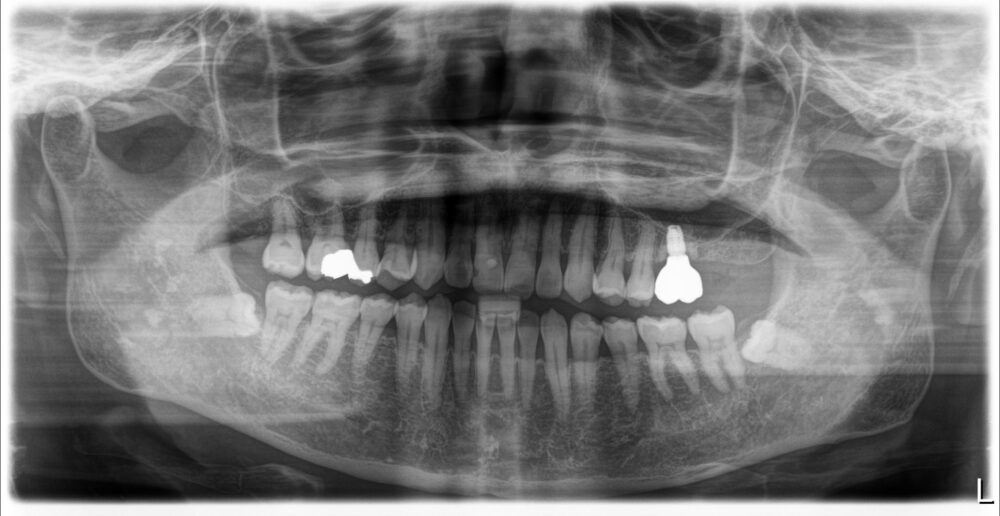

症例3

治療前

| 主訴 | 歯を入れたい |

| 診断 |

「右下」67欠損 |

| 治療内容 | 右下67左下6インプラント、左上⑤6⑦ジルコニアブリッジ |

| 年齢・性別 |

68歳 男性 |

| 治療期間 |

8ヶ月 |

| 治療費用 | ①左上⑤6⑦ジルコニアブリッジ¥264000 ②右下67左下6インプラント(3本) 診査診断¥22000+一次手術(京セラ)¥825000+左下6GBR¥110000+上部構造¥429000 総額¥1386000 |

| リスク・副作用 | インプラント周囲炎、インプラント上部構造の緩み |